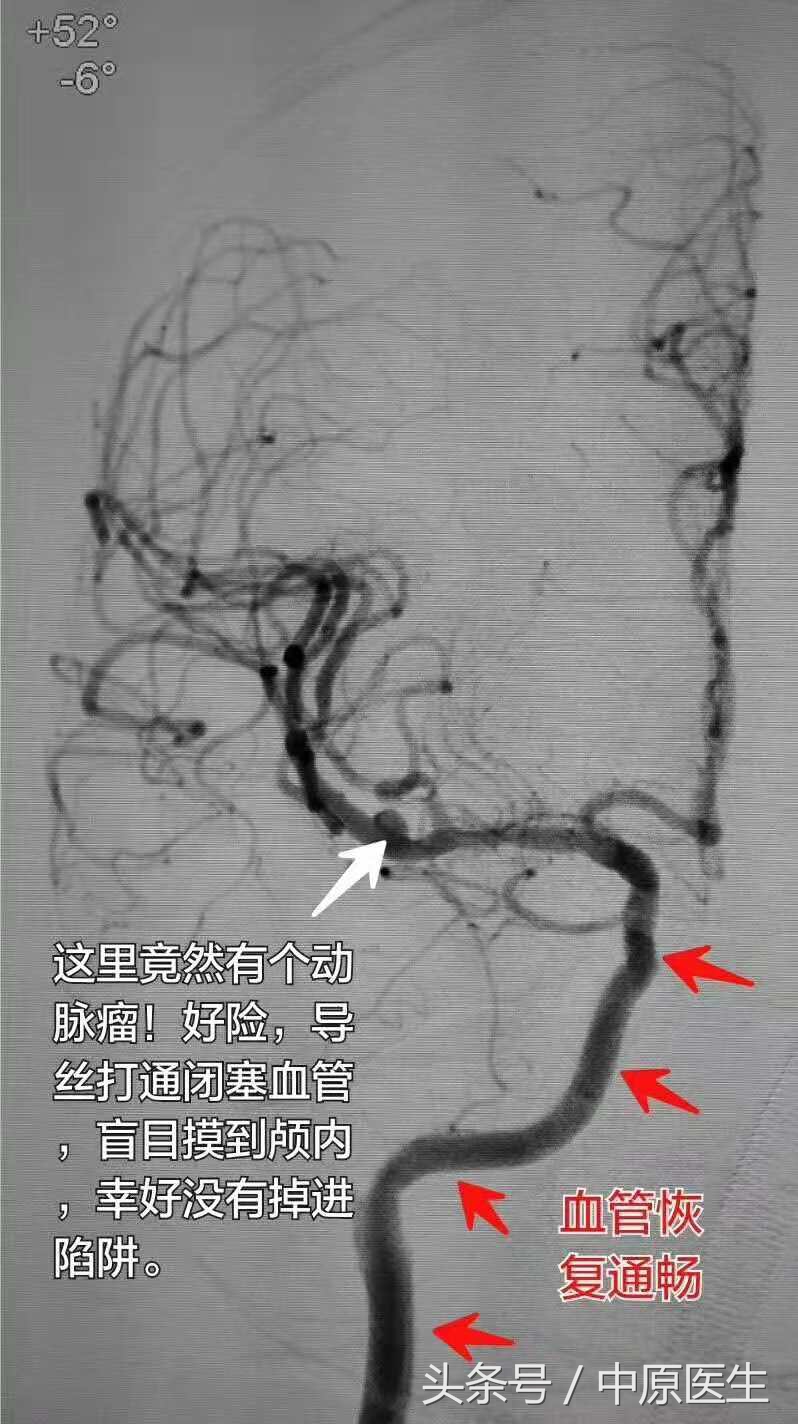

感谢病人家属的信任(不论成败,强烈要求我们手术尝试),通过艰苦的努力,成功打通了血管。术后血管造影吓出一身冷汗:他颅内有个动脉瘤!由于血管是闭塞的,事先不知道啊!要是盲目摸进动脉瘤腔,捅破了动脉瘤,老天爷,那才是不堪设想。

没敢直播,感谢许奕教授洪波教授黄清海教授同意我们做了录播。感谢许小勤蔡小阳术中出的热汗,和我术后出的冷汗。